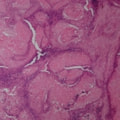

骨生検および病理組織検査

レントゲン検査所見から、骨もしくはその周囲組織に発生した腫瘍の可能性が考えられたため、病変部の細胞診検査およびジャムシディ生検針を用いた病変の骨生検を実施した。病理組織検査の結果、非上皮性の悪性腫瘍である“肉腫”と診断された。